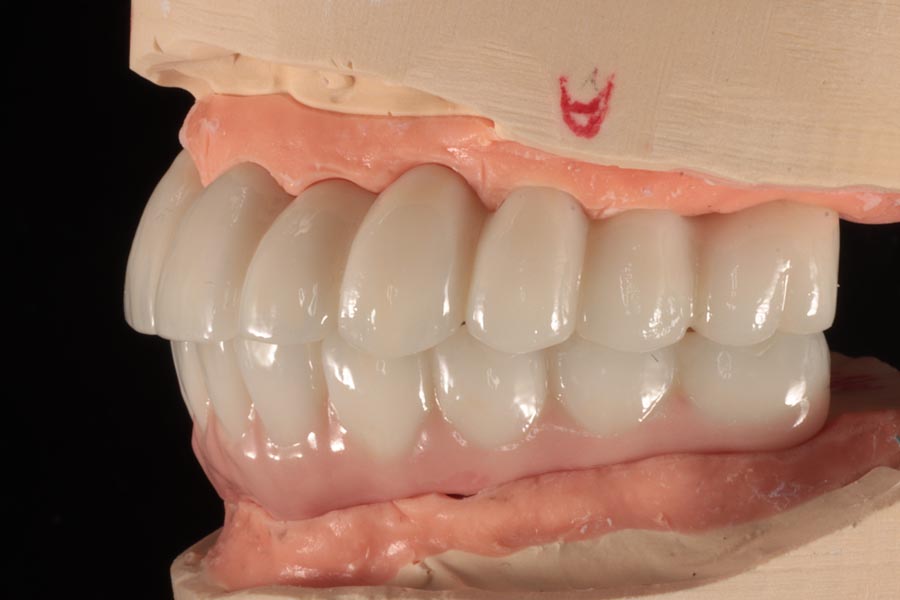

Prototypes are design and fabricated in wax so we can dial in the esthetics that we are looking for. In this particular case, a little pink was designed on the lower to compensate for tissue resorption while keeping tooth length proportional and balanced.

Once the final design is approved, the lab begins fabricating definitive restorations. They are able to add a lot more character and definition at this stage, resulting in restorations that are beautiful and realistic.

More importantly, special care is taken to ensure the tissue-fitting surfaces are smooth and convex. This ensures that any plaque that builds up here is easily removed with regular brushing and water-picking. Hygiene is important for long-term tissue health and this implant success.